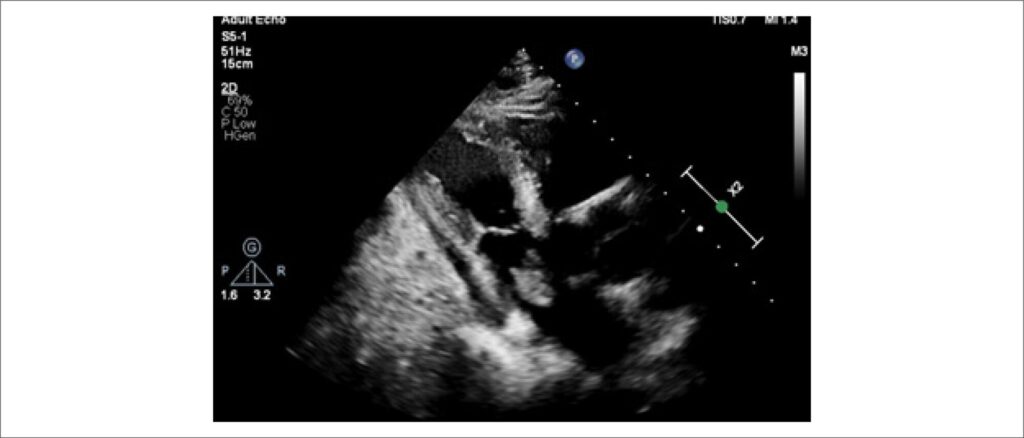

Atrial Myxoma as a Rare Cause of Stroke: Case Report

Atrial myxoma (AM) is the most common primary benign tumor affecting the heart. Its prevalence is rare, estimated at 0.03% in the general population. Surgical intervention should be introduced as soon as diagnosed due to the increased risk of cardiac complications, such as intracardiac obstructions or systemic embolizations.

Cardiac myxomas are commonly observed in the left atrium in >75% of cases, predominantly attached with a stalk to the fossa ovalis (>90%). However, they can be seen in other locations (left ventricle, right atrium, and, though quite rarely, the right ventricle).